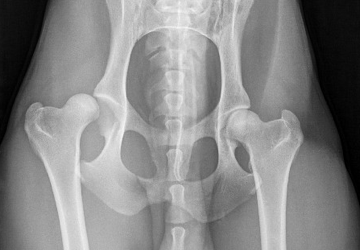

Osteoarthritis

Osteoarthritis is a common cause of lameness and reduced mobility in our pets.